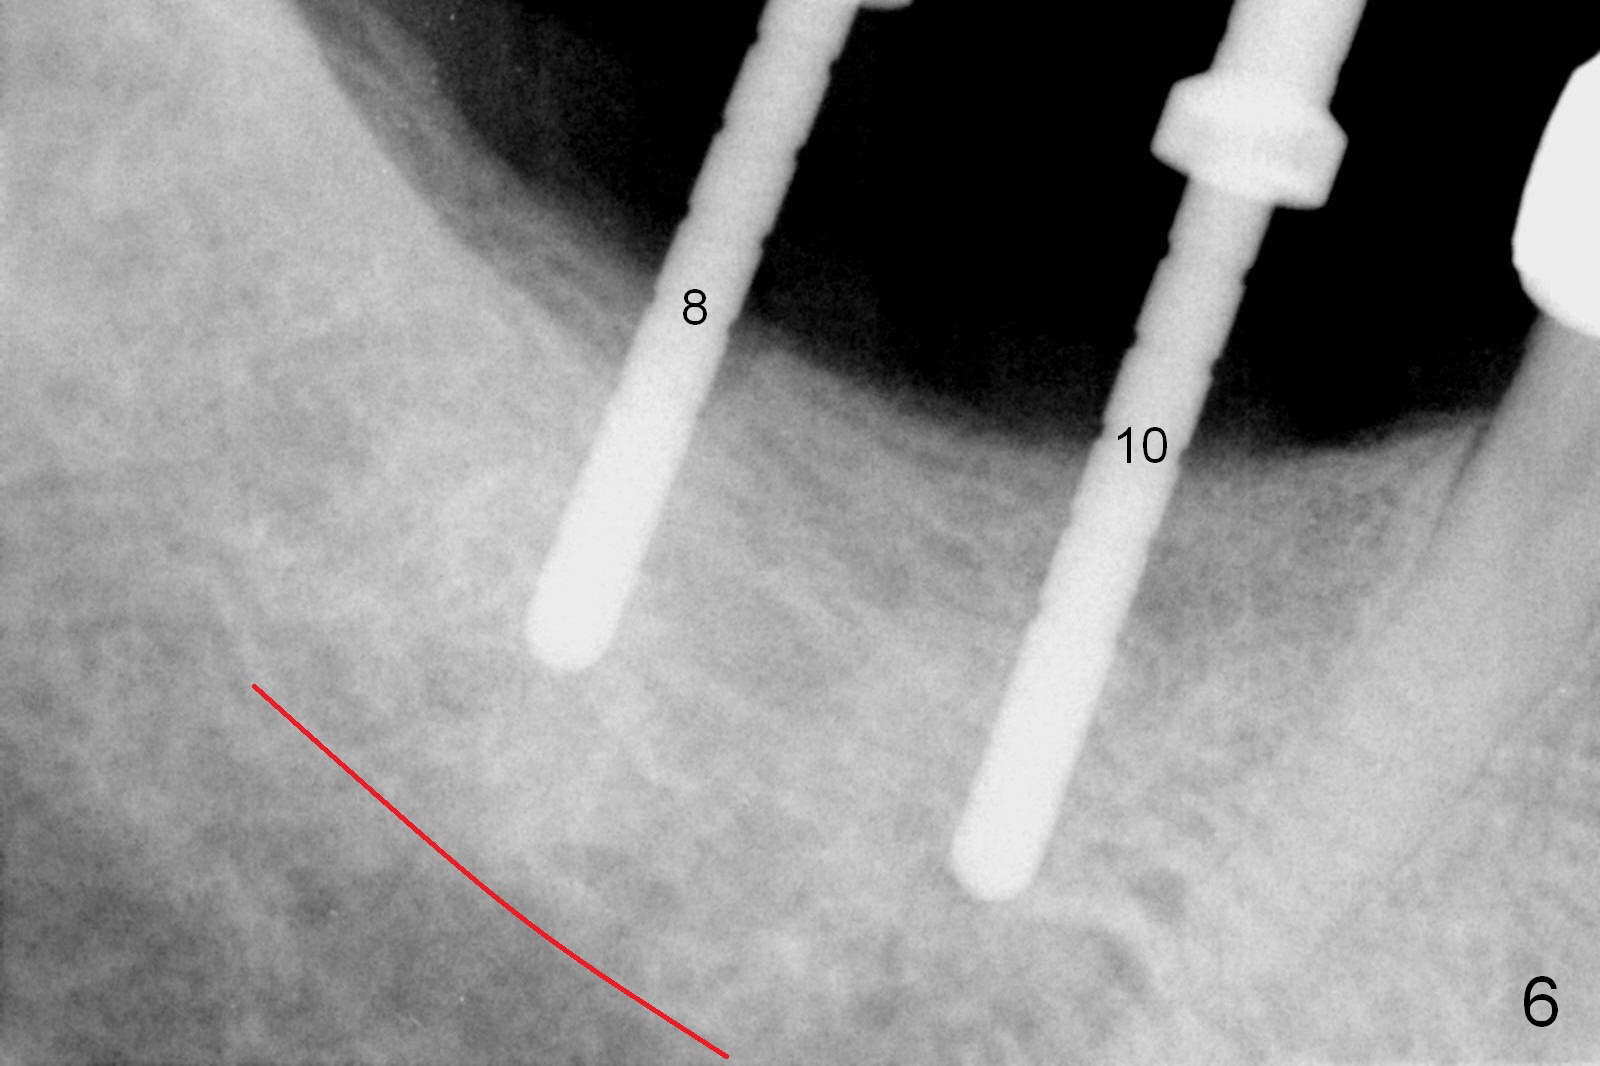

In fact, initial depth for #18 and 19 is 12 mm, quite close to the Inferior Alveolar Canal at #18 (Fig.3 (red dashed line: the superior border of the former). By mistake, the implant at #18 is placed a little deeper than necessary, since the buccal bone is inferior to the lingual one (Fig.4; 5.3x12 mm vs. 5.0x12 mm for #19). As planned, panoramic X-ray is taken immediately postop. Bone height at the 2nd molar decreases drastically as compared to that of the 1st molar, especially on the right side (Fig.5 (abutments: 6.8x5(2) mm for #19, 7.8x5(3) for #18, respectively)). For #30,31 implant placement, initial depth will be 10 and 8 mm, respectively. Follow it faithfully. The implant at #31 could be as large as 5.9 or 6.4 mm to compensate for the length.

One month later, the patient returns for #30 and 31 implant placement. As planned, the initial depth is 10 and 8 mm (Fig.6). What is unexpected is deficiency in ridge width. Narrower implants (as compared to those on the left) are placed (Fig.7: 4.5x12 and 4.5x10 mm). With shorter implants, the implants are later placed deeper (as shown by arrows in Fig.7) so that almost all of the microthreads are buried in the bone. It is expected that there is less chance of thread exposure postop. The later turns out to be true 3.5 months postop (Fig.8 with 6.8x5(3) mm abutments). It appears that the abutment margin is supragingival (white dashed line: gingival margin) and should be trimmed prior to impression. Or change the abutments to ones with shorter cuff. It may be so for those at #18 and 19 (Fig.9: 4 months postop). Custom full arch trays will be used for impression with bite registration. In fact the mesial margin of #19 abutment is ~ 2 mm subgingival. A longer-cuff abutment is used (6.8x5(3) mm) at #19 before impression.